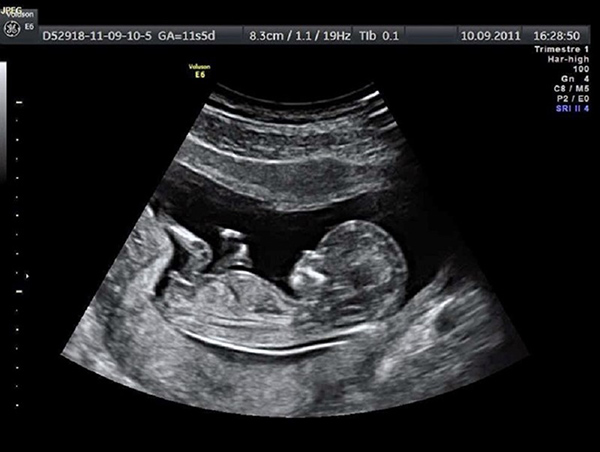

Siêu âm là một phương thức được sử dụng phổ biến đối với những mẹ bầu đang mang thai. Siêu âm gồm nhiều loại như siêu âm 2D, 3D, 4D trong đó thì siêu âm 2D được xem là loại siêu âm đen trắng. Với hình thức siêu âm này cũng giúp các bác sĩ có thể theo dõi được sự phát triển của thai nhi cùng những bất thường xảy ra trên cơ thể bé.

Đây là phương pháp siêu âm được xem và cổ tuy nhiên vẫn được sử dụng trong siêu âm thai nhi hiện nay. Tuy nhiên, với hình thức siêu âm 2D này thì thường chỉ áp dụng cho thai nhi dưới 20 tuần tuổi. Để có thể kiểm tra vị trí của thai, hay những vấn đề bất thường có trên thai nhi.

Phương pháp siêu âm đen trắng này các bác sĩ cũng đo được kích thước trong buồng tử cung của chị em. Kích thước của thai nhi từ đầu đến chân hoặc các bộ phận khác. Với hình thức siêu âm này các mẹ cũng nắm chắc được sự phát triển từng bộ phận của thai nhi.